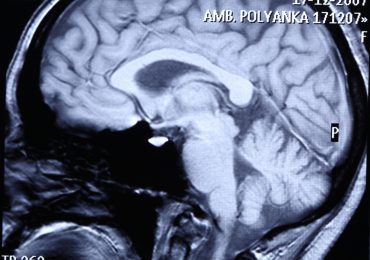

Een motivatiecentrum geïdentificeerd in de hersenen

Welk structureel element van de hersenen is betrokken bij de motivatie tijdens een actie van fysieke en mentale inspanningen? Volgens een team Franse onderz…